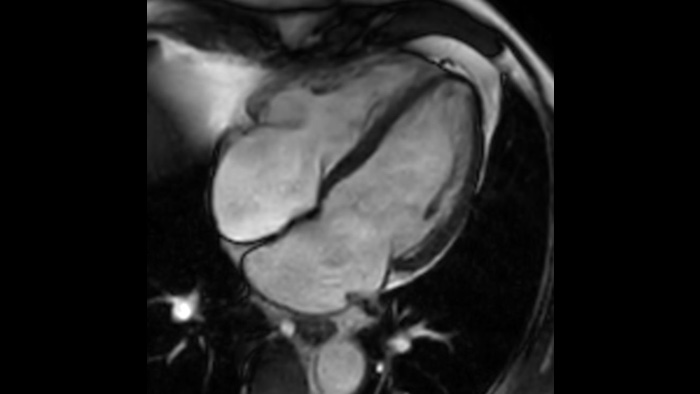

Medio cardíaco

Comodidad del paciente

Proporciona una reducción de hasta un 40% en las apneas, con una calidad de imagen prácticamente igual. 3